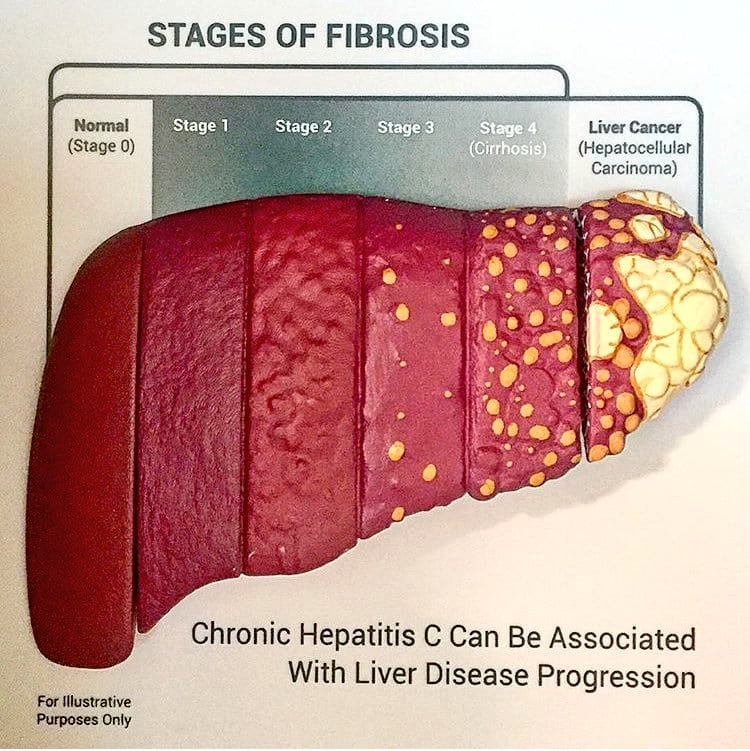

Stages of Liver Damage, Illustration – Stock Image – C027/6479 …

Stages of liver damage. Starting from a healthy liver (top left Stock …